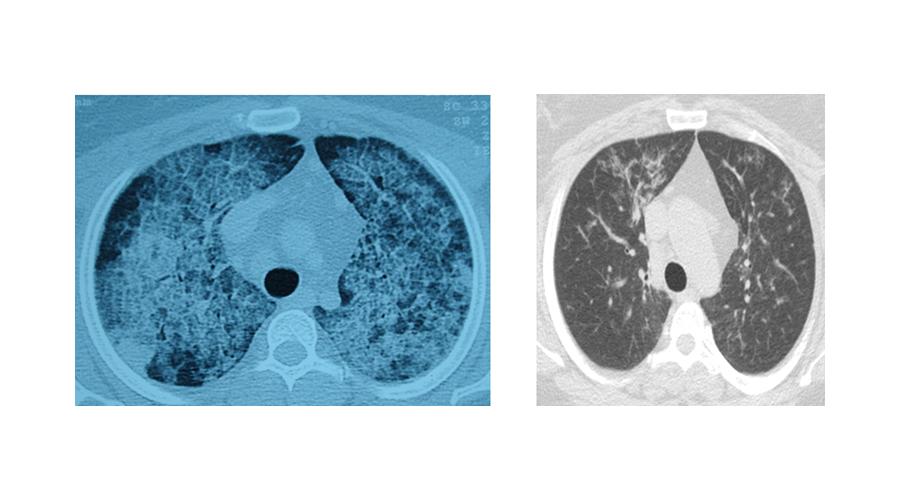

Hastalığın, kişinin kendi yağ ve proteinlerinin temizlenmesiyle görevli hücrelerdeki sorun nedeniyle akciğerlerdeki hava keseciklerinin birikmesi sonucu ortaya çıktığını aktaran Ergur, belirtilerin nefes darlığı, yorgunluk ve aşırı halsizlik olduğunu kaydetti.

Ergur, hastalığın çoğu zaman astımla karıştırıldığını, tanının ancak ileri tetkiklerle konulabildiğini ifade etti.